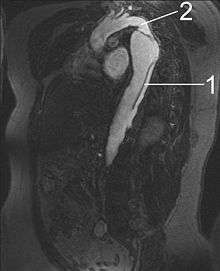

In medical pathology, a dissection is a tear within the wall of a blood vessel, which allows blood to separate the wall layers. By separating a portion of the wall of the artery (a layer of the Tunica intima or tunica media), a dissection creates two lumens or passages within the vessel, the native or true lumen, and the "false lumen" created by the new space within the wall of the artery.